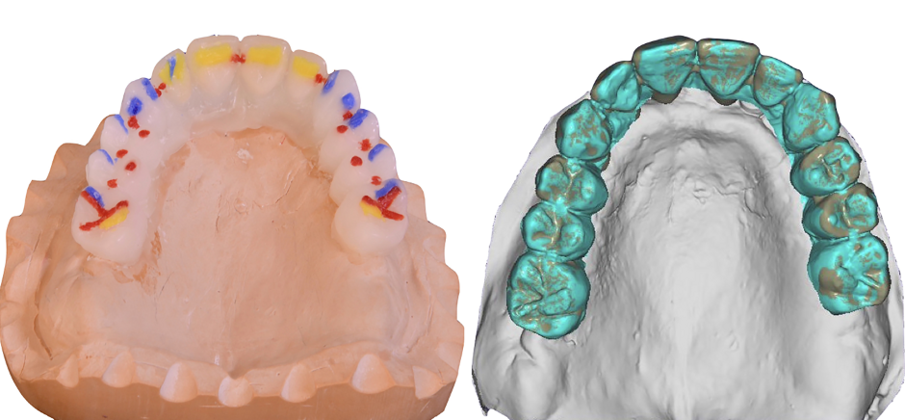

Dopo due mesi è stata eseguita una scansione (Fig. 11) e i modelli in stampa 3D successivamente prodotti sono stati zoccolati per articolatore e ri-virtualizzati (Fig. 12) utilizzando un desktop scanner (inEos X5, Dentsply Sirona). I rapporti intermascellari e la posizione degli impianti sono stati accuratamente registrati, duplicando le protesi provvisorie in resina trasparente e fissando in bocca le posizioni dei transferts sui duplicati. La passività e precisione dei transferts in occlusione devono in questa fase essere controllate con estrema accuratezza. L’occlusione dei duplicati è usata quindi per il montaggio dei modelli zoccolati, che sono stati fissati su basi di montaggio con un arco facciale in un articolatore arcon completamente regolabile (Reference SL, Gamma Dental).